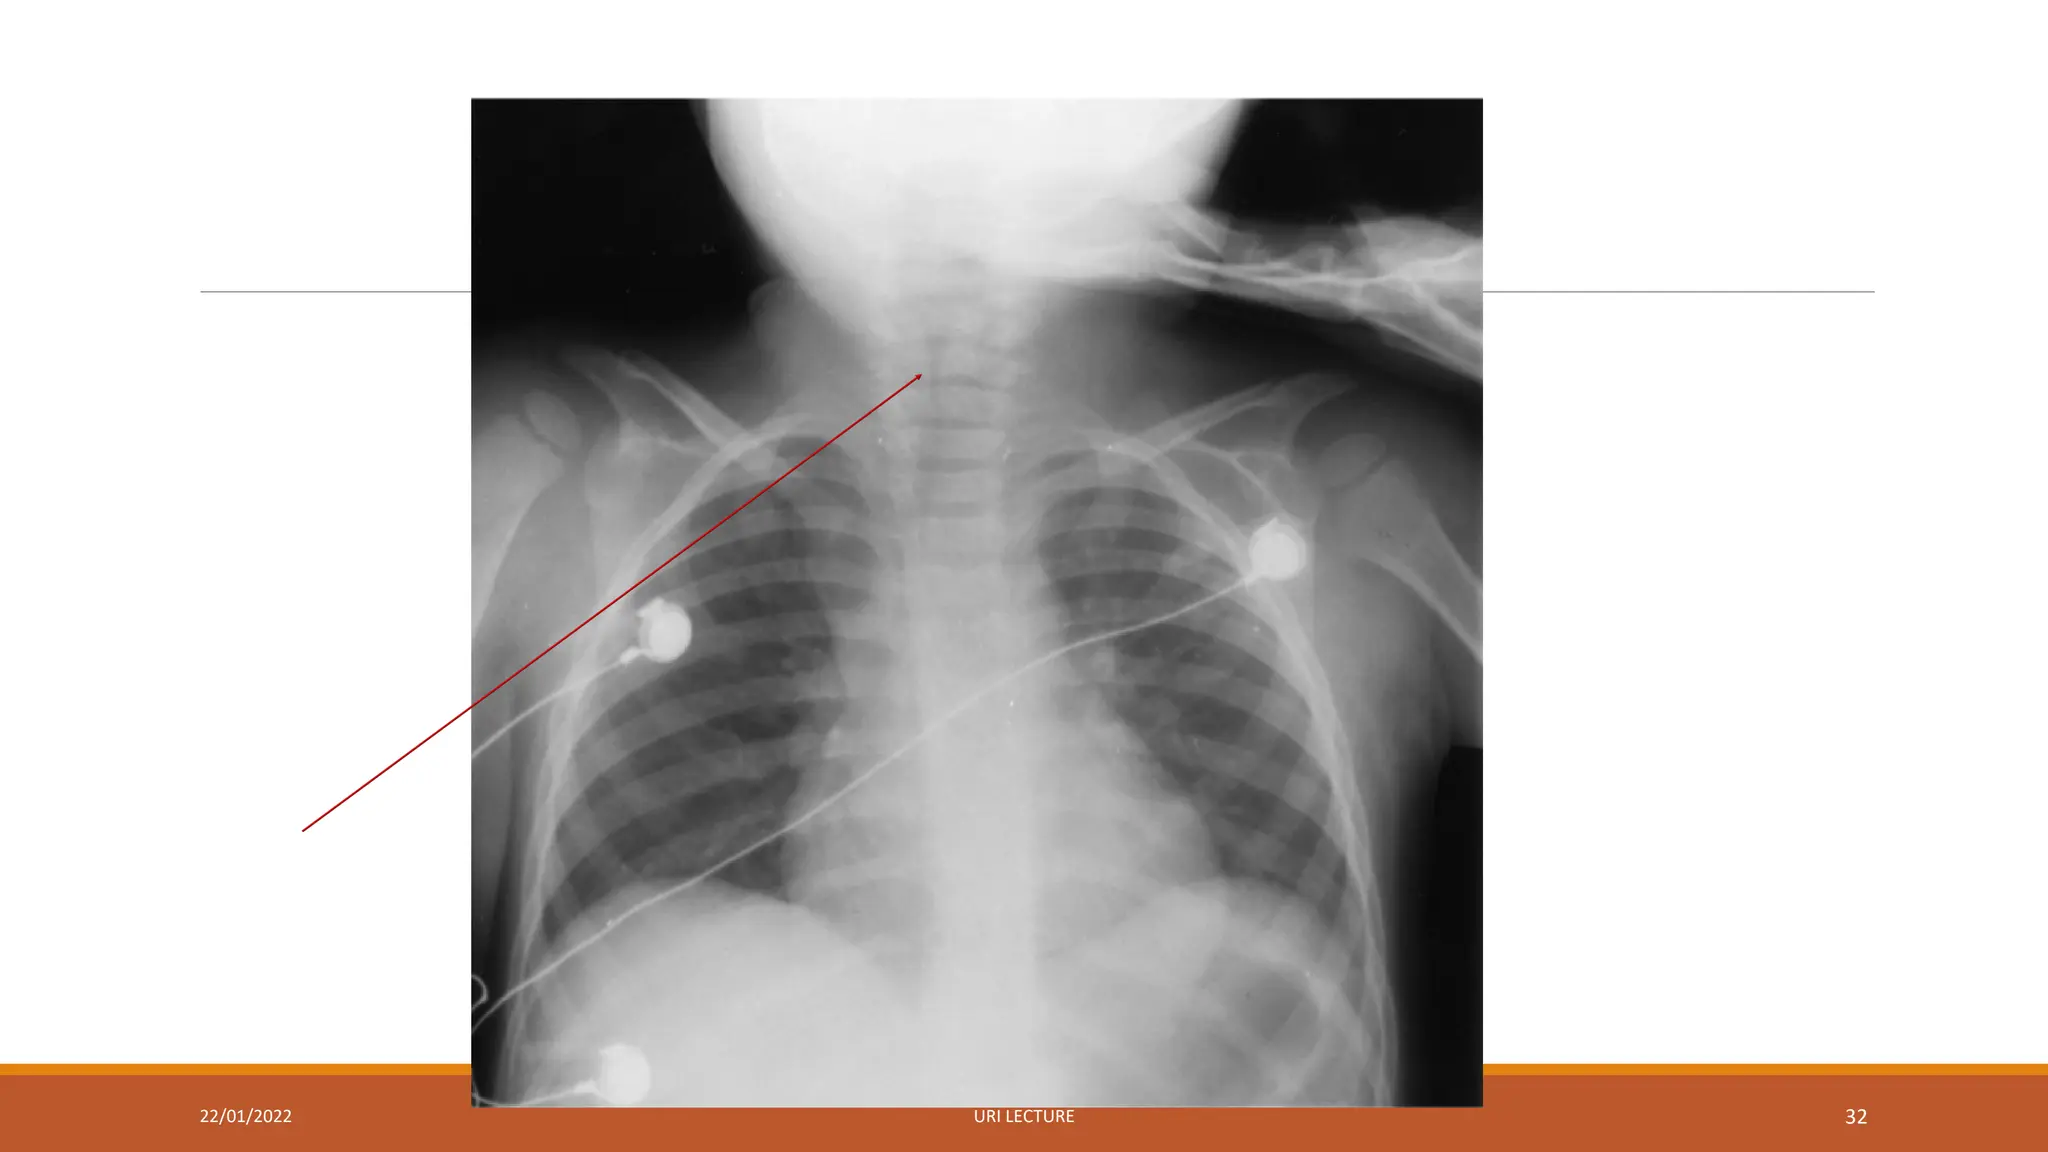

Diagnosis of LTB

The diagnosis is clinical

X-rays may show the typical subglottic narrowing

Diagnosis of LTB Thediagnosis is clinical X-rays may show the typical subglottic narrowing 22/01/2022 URI LECTURE 31

• 31.